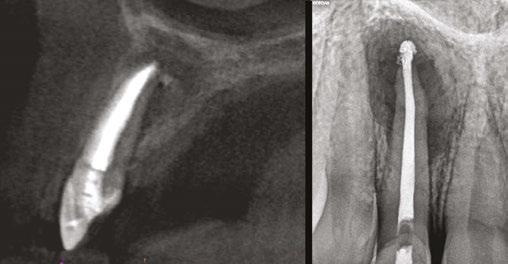

Judy McIntyre, DMD, MS Figure 1: Acutely curved and calcified buccal canal right under upper left premolar crown margin; valuable information for access and management. No. 9 also has a PARL, which was only incidentally captured Figure 2: Large PARL with destruction of the maxillary sinus floor and sinusitis as a result

About 10 years after completing residency, I opened my own practice and invested in a DEXIS CBCT. Initially, I only used it for apicoectomies and retreatments. In time, I began to realize how helpful it was for all my cases. With the 3D-scan information (Figure 1), I could have saved myself some humbling experiences and surprises. Endodontists hate surprises, and we really hate failures! Once I started using my CBCT more frequently, I was able to appreciate things that would have otherwise been intra-op surprises and plan for them prior to starting the procedure. The 3D data allows me to properly assess prognosis, determine the best course of treatment, and plan that treatment with a level of precision that is impossible otherwise.